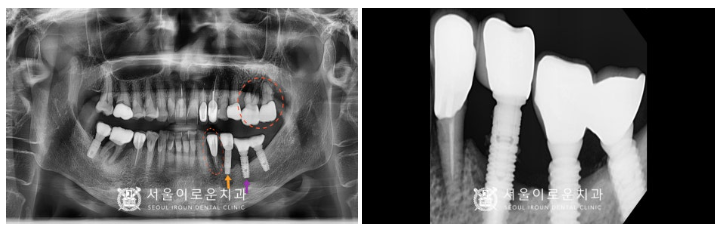

먼저 위턱 왼쪽 어금니 두 개(#26,27) 발치 후

염증을 깨끗하게 제거해주었습니다.

염증이 남아있게 되면

임플란트가 단단하게 고정되지 못하고

추후 금방 탈락하는 등

부작용이 생길 수 있기 때문에

염증조직을 남기지 않고

깨끗하게 제거하는데 집중하였습니다.

염증조직 제거를 마무리하고

임플란트 즉시 식립 후

염증으로 인해 뼈가 흡수된 부분에

뼈이식을 같이 진행하였는데요.

뼈이식 후 차폐막을 대어

이식한 뼈가 빠져나오지 않고

안정적으로 자리 잡아

잘 유지될 수 있도록 해주었답니다.

그리고 아래턱 왼쪽 첫 번째

작은 어금니(#34) 발치와

두 번째 작은 어금니 임플란트(#35) 제거 후

마찬가지로 염증조직을

깨끗하게 제거한 뒤

(#34) 부위에

임플란트 즉시 식립을 진행하였으며,

해당 부위도 위와 마찬가지로

뼈이식 및 차폐막을 활용하여

수술을 진행했습니다.

또한 첫 번째 어금니 기존 임플란트(#36)는

치은박리소파술로

염증 제거를 도와드렸습니다.